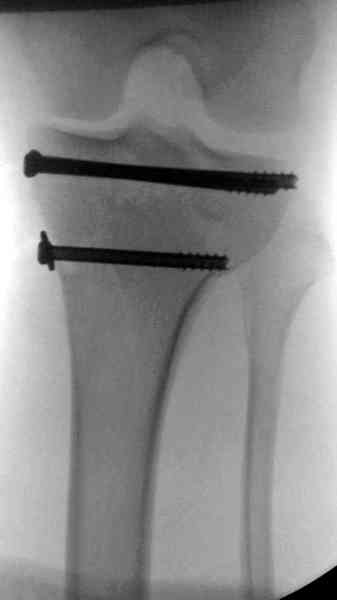

При высокоскоростных переломах редко можно встретить изолированную травму пилона, и в моей практике изолированные травмы большая редкость, поэтому, как дополнение к обсуждаемой теме, решил представить свежий, двухдневной давности случай.

Предыдущей сменой до 4:00 утра по поводу открытого перелома бедра, тибиал плато, пилон и надколенника сделана операция.

Пострадавшему 21 г., травма скоростная, после I&D с расширением раны, на бедре сделана операция ретроградным интрамедуллярным штифтом, остеосинтез с частичной резекцией надколенника и ушивание собственной связки.

В настоящее время больной в реанимации по поводу Черепно Мозговой Травмы и состояние улучшается. Запланировал ушивание раны в пятницу, если позволит состояние мягких тканей и при отсутстви отека возможно удастся просунуть перкутанномедиальную пластину.